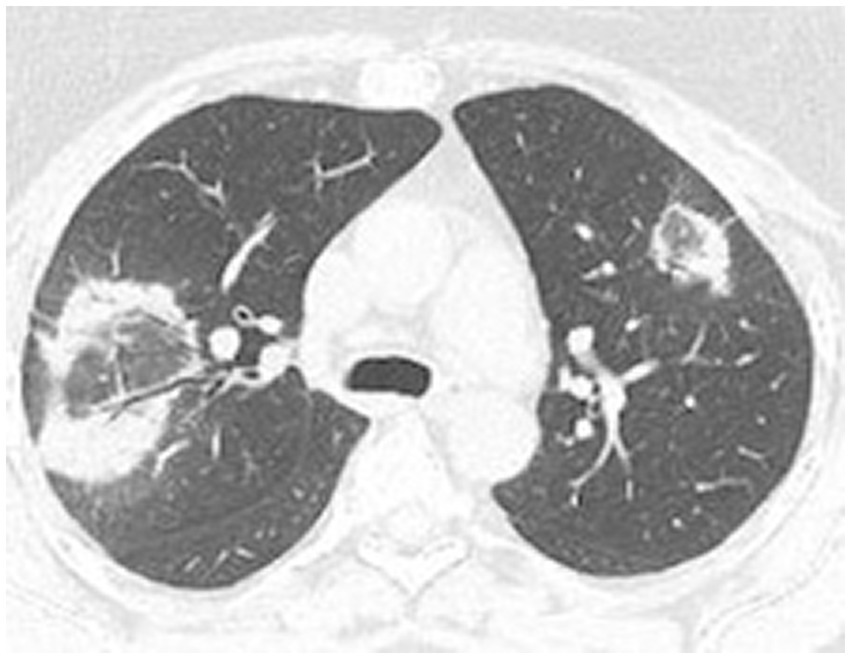

High-resolution computed tomography (HRCT) is the gold standard in the evaluation of OP. It reveals multifocal areas of consolidation, often with a characteristic air bronchogram. Additionally, patchy alveolar consolidations, nodules, areas of ground glass opacity, perilobular infiltrations, bronchial wall thickening, and reticular fibrous changes may be present in peripheral parts of both lungs. Thickening around areas of ground glass opacity with an “atoll” or “crazy-paving” pattern may also be present, although it is less common. Additionally, nodular lesions, pleural thickening, and rarely enlargement of hilar and mediastinal lymph nodes, are present; emphysema or pleural effusion may also be observed (28–40). Honeycomb-type lesions are not in the spectrum of pulmonary changes observed in COP but might be evident in patients who exhibit interstitial pulmonary fibrosis with a component of OP (Figures 2–6).

High resolution computed tomography scan of a patient with COP. Bilateral ground glass opacities with associated peripheral consolidations forming an atoll sign.